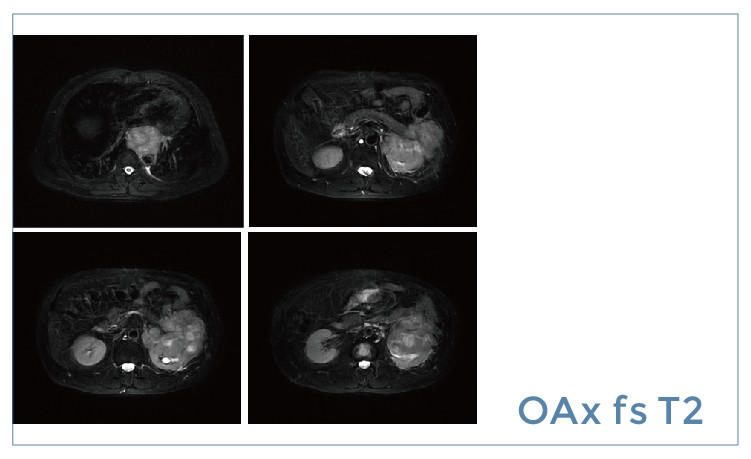

【朗润影像档案】20190531磁共振影像病例结果讨论

【朗润影像档案】磁共振影像病例分享(编号20190531)